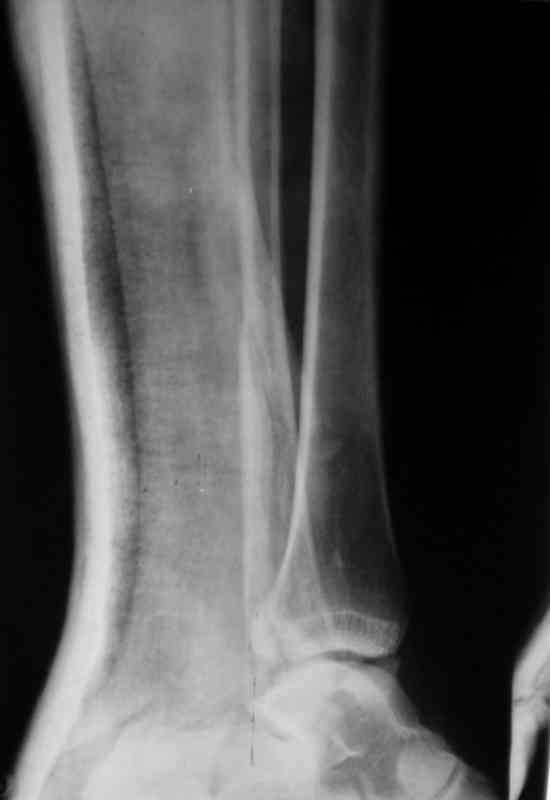

Вот рентгенконтроль на 7-е сутки после репозиции.

Стандартными снимками считается прямая, боковая и мортиз!!!, а так трудно гадать, насколько потеря длины малоберцовой. На боковом снимке не сопоставленный перелом медиальной лодыжки и перелом заднего края без смещения.

Трехлодыжечные переломы относятся к нестабильным переломам, при вовлечении перелома заднего края больше 15% суставной поверхности и смещения более 2 мм тогда такие переломы необходимо оперировать.

Хорошо сопоставленная закрытая репозиция отломков не гарантирует отличный окончательный результат.

Трудно удержать трехлодыжечные переломы задней лонгетной повязкой (на снимке), а последующие долгие гипсовые повязки могут привести к контрактурам.

Оперативное лечение предупреждает артроз из-за ранних движений, и больные восстанавливается быстрее, чем на консервативном лечении.

Вероятность ошибки при оценке состояние сустава без стандартных снимков возрастает на 30%, поэтому необходимо добиться от рентгенолога всех необходимых снимков.